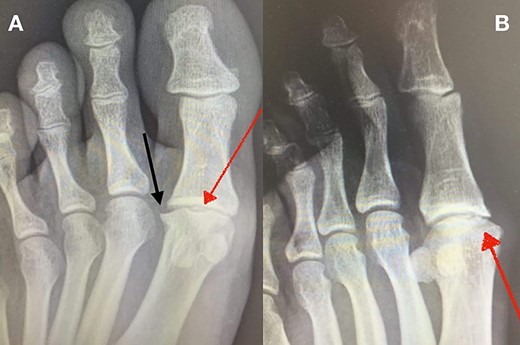

MRI (sagittal view) of the left foot. The red dots show a deep MH defect involving the subchondral bone, a typical finding of OD.

Standing anteroposterior (AP), oblique and lateral radiographs of the affected foot were taken. On the AP and oblique views, an OD lesion of the 1st MH was visible (lytic lesion of the subchondral bone and subchondral sclerosis formation) with a lateral-forming osteophyte (Fig. 1A and B). Magnetic resonance imaging (MRI) of the left foot clearly shows the osteochondral defect of the 1st MH (Figs 2 and 3).